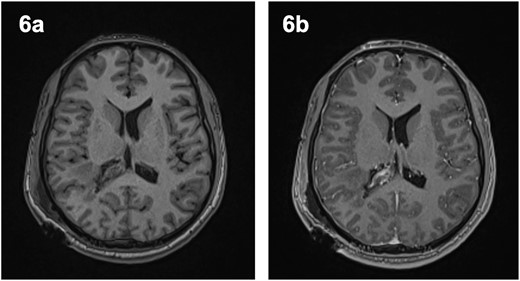

Post-operative course

The patient remained neurologically intact post-operatively and was discharged 5 days after surgery. A post-operative MRI revealed some intraventricular enhancement but no clear residual tumour (Fig. 5), likely indicating a complete resection of the lesion. He was seen in clinic 4 days and again 3 months after discharge and was noted to be recovering well.

Post-operative magnetic resonance imaging revealed evidence of intraventricular enhancement, with no distinct lesion identified on axial T1-weighted imaging pre- (6a) and post-contrast (6b).